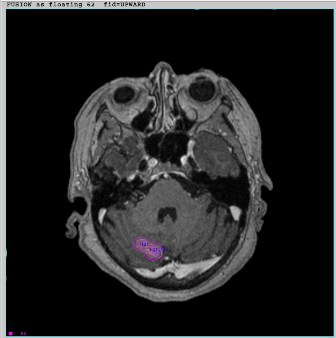

La radiocirugía estereotáxica (SRS), A pesar de su nombre, y en comparación con la radioterapia tradicional, es un procedimiento no quirúrgico que entrega una alta dosis de radiación focalizada en la lesión intracerebral en un número limitado de fracciones (1-4).

Es una técnica de radioterapia sumamente precisa con un margen de error submilimétrico, inicialmente desarrollada para tratar lesiones tumorales pequeñas y anomalías funcionales y/o vasculares del cerebro.

La Radiocirugía es realizada con un Acelerador Lineal dedicado. El Acelerador Lineal o LINAC, (por sus siglas en inglés) genera rayos-x de alta energía, los cuales son dirigidos hacia el tumor desde un gran número de ángulos, protegiendo los tejidos sanos aledaños. La técnica requiere inmovilización del paciente mediante un marco estereotáxico.